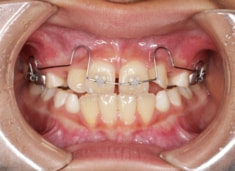

治療前

治療開始時